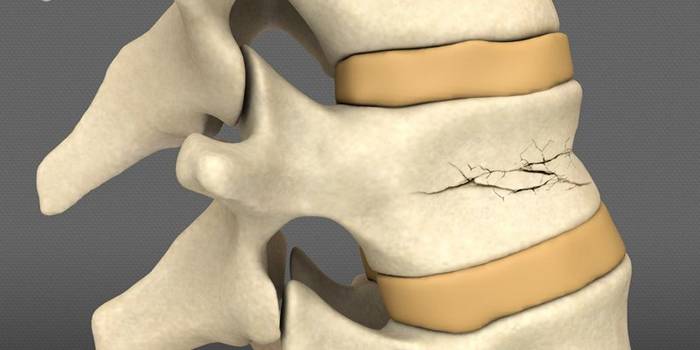

Визуализация трещины на фоне перелома позвонка

Диагностика

Для того чтобы выявить нарушения структуры кости, нужно собрать анамнез заболевания, жалобы, провести осмотр и отправить на дополнительные методы обследования. Для подтверждения нарушений структуры позвонков проводится рентгеновский снимок. На нем можно заметить линию разлома кости, наличие смещения мелких осколков. Также возможно проведение компьютерной томографии, МРТ.